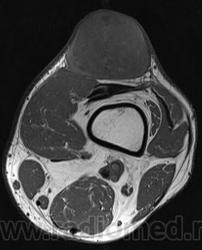

При осмотре атерома представляет собой опухолевидное образование округлой формы, мягкой консистенции размером от 5 до 40 мм и более. Кожа над атеромой обычно не изменена, однако в случае присоединения воспаления может иметь красноватый оттенок. Атерома подвижна вместе с окружающими тканями, безболезненна. Атерома может оставаться маленькой на протяжении многих лет, либо увеличиваться.

Иногда атерома сообщается с поверхностью кожи через небольшое отверстие, через которое могут отделяться атероматозные массы. Часто атеромы нагнаиваются, кроме этого, может происходить разрыв атеромы в подкожную клетчатку.